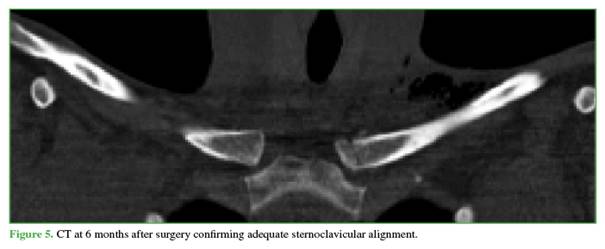

Postoperative management consisted of sling immobilization for 40 days and immediate elbow flexion–extension and pronation–supination exercises. At 2 weeks, the patient began physical therapy and pendulum exercises, with complete restriction of adduction and flexion/abduction less than 90°. After 6 weeks, the sling was removed and range of motion was released; resisted strengthening began at 3 months. At 6 months, CT was normal (Figure 5) and the patient was cleared for contact sports.